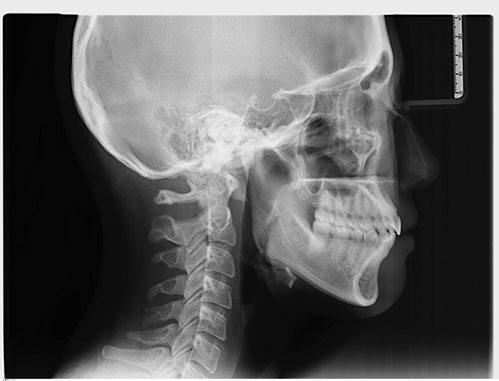

側顱X光攝影(Cephalometric x-ray) 是一張從側面拍攝頭顱骨及軟組織之X光片,主要用於齒顎矯正術前、術後評估用,並利用它繪製出矯正分析圖(Cephalometric Tracing),取得頭顱與齒列的測量值(Means),牙醫師則依據這些測量值進行評估患者是屬於何種咬合類型,同時配合其他X光攝影 ( 如:全口掃描、正頭顱、手骨‧ ‧ ‧ ‧ ‧ ‧ ),來執行矯正治療計畫。